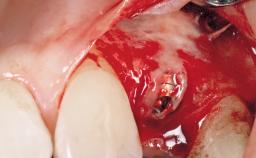

A 30-year-old female patient had lost tooth 21 and was referred to our clinic for consultation and treatment. Due to advanced apical infection, tooth 21 had been extracted two months earlier at another clinic and an acrylic-resin tooth had been bonded to the adjacent teeth. The patient desired implant treatment to avoid any damage to the adjacent natural teeth. While the patient had no history of any systemic disorder, she was a heavy smoker and exhibited medium to advanced periodontitis in the entire jaw. After the initial treatment to achieve a pocket probing depth of less than 4 mm and no bleeding on probing, a decrease in the height of the papillae mesial and distal to the extraction site and overall gingival recession were observed.

| Bone Augmentation | Horizontal|Staged |

| Augmentation Materials | Autogenous chips|Membrane |